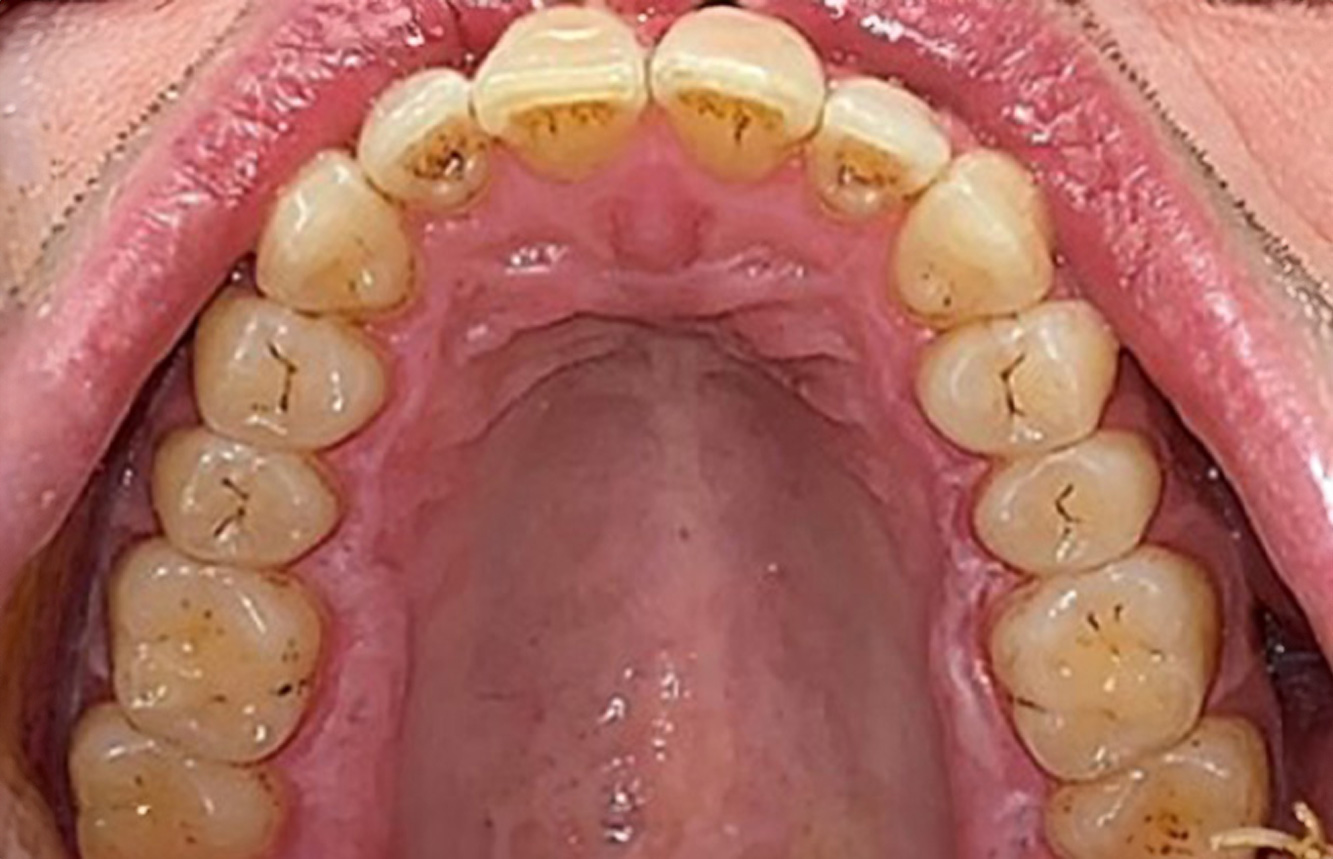

Cazuri pacienți conform IPC

Următoarele studii de caz* acestea au rolul să ilustreze interacțiunea dintre necesitățile și factorii de risc definiți pentru IPC, precum și efectele factorilor individuali.

The healthy patient with pre-existing periodontal disease & peri-implantitis

A 52-year-old patient presents at a preventive care session. The patient has no systemic disease and is not taking any medication. He has had various dental treatments and also has two active carious lesions. In addition, the patient has four implants (2nd, 3rd and 4th quadrants). He is revealed to have early periodontal disease (stage IV, grade B). His periodontal condition is stable; a probing depth of Probing depths (ST) of 5 mm is only evident at the implant in region 36. Gingivitis is also identified. more